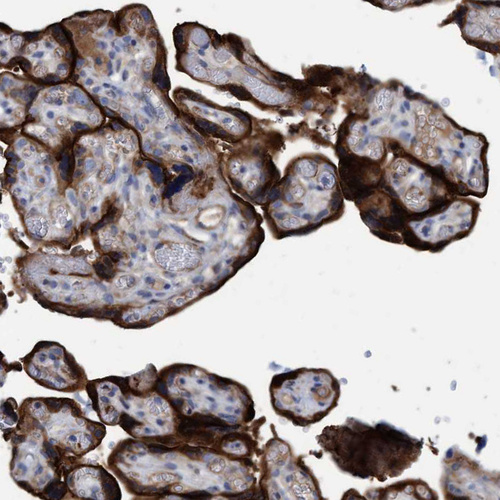

Immunohistochemistry analysis in human placenta and lymph node tissues using HPA020587 antibody. Corresponding GULP1 RNA-seq data are presented for the same tissues.